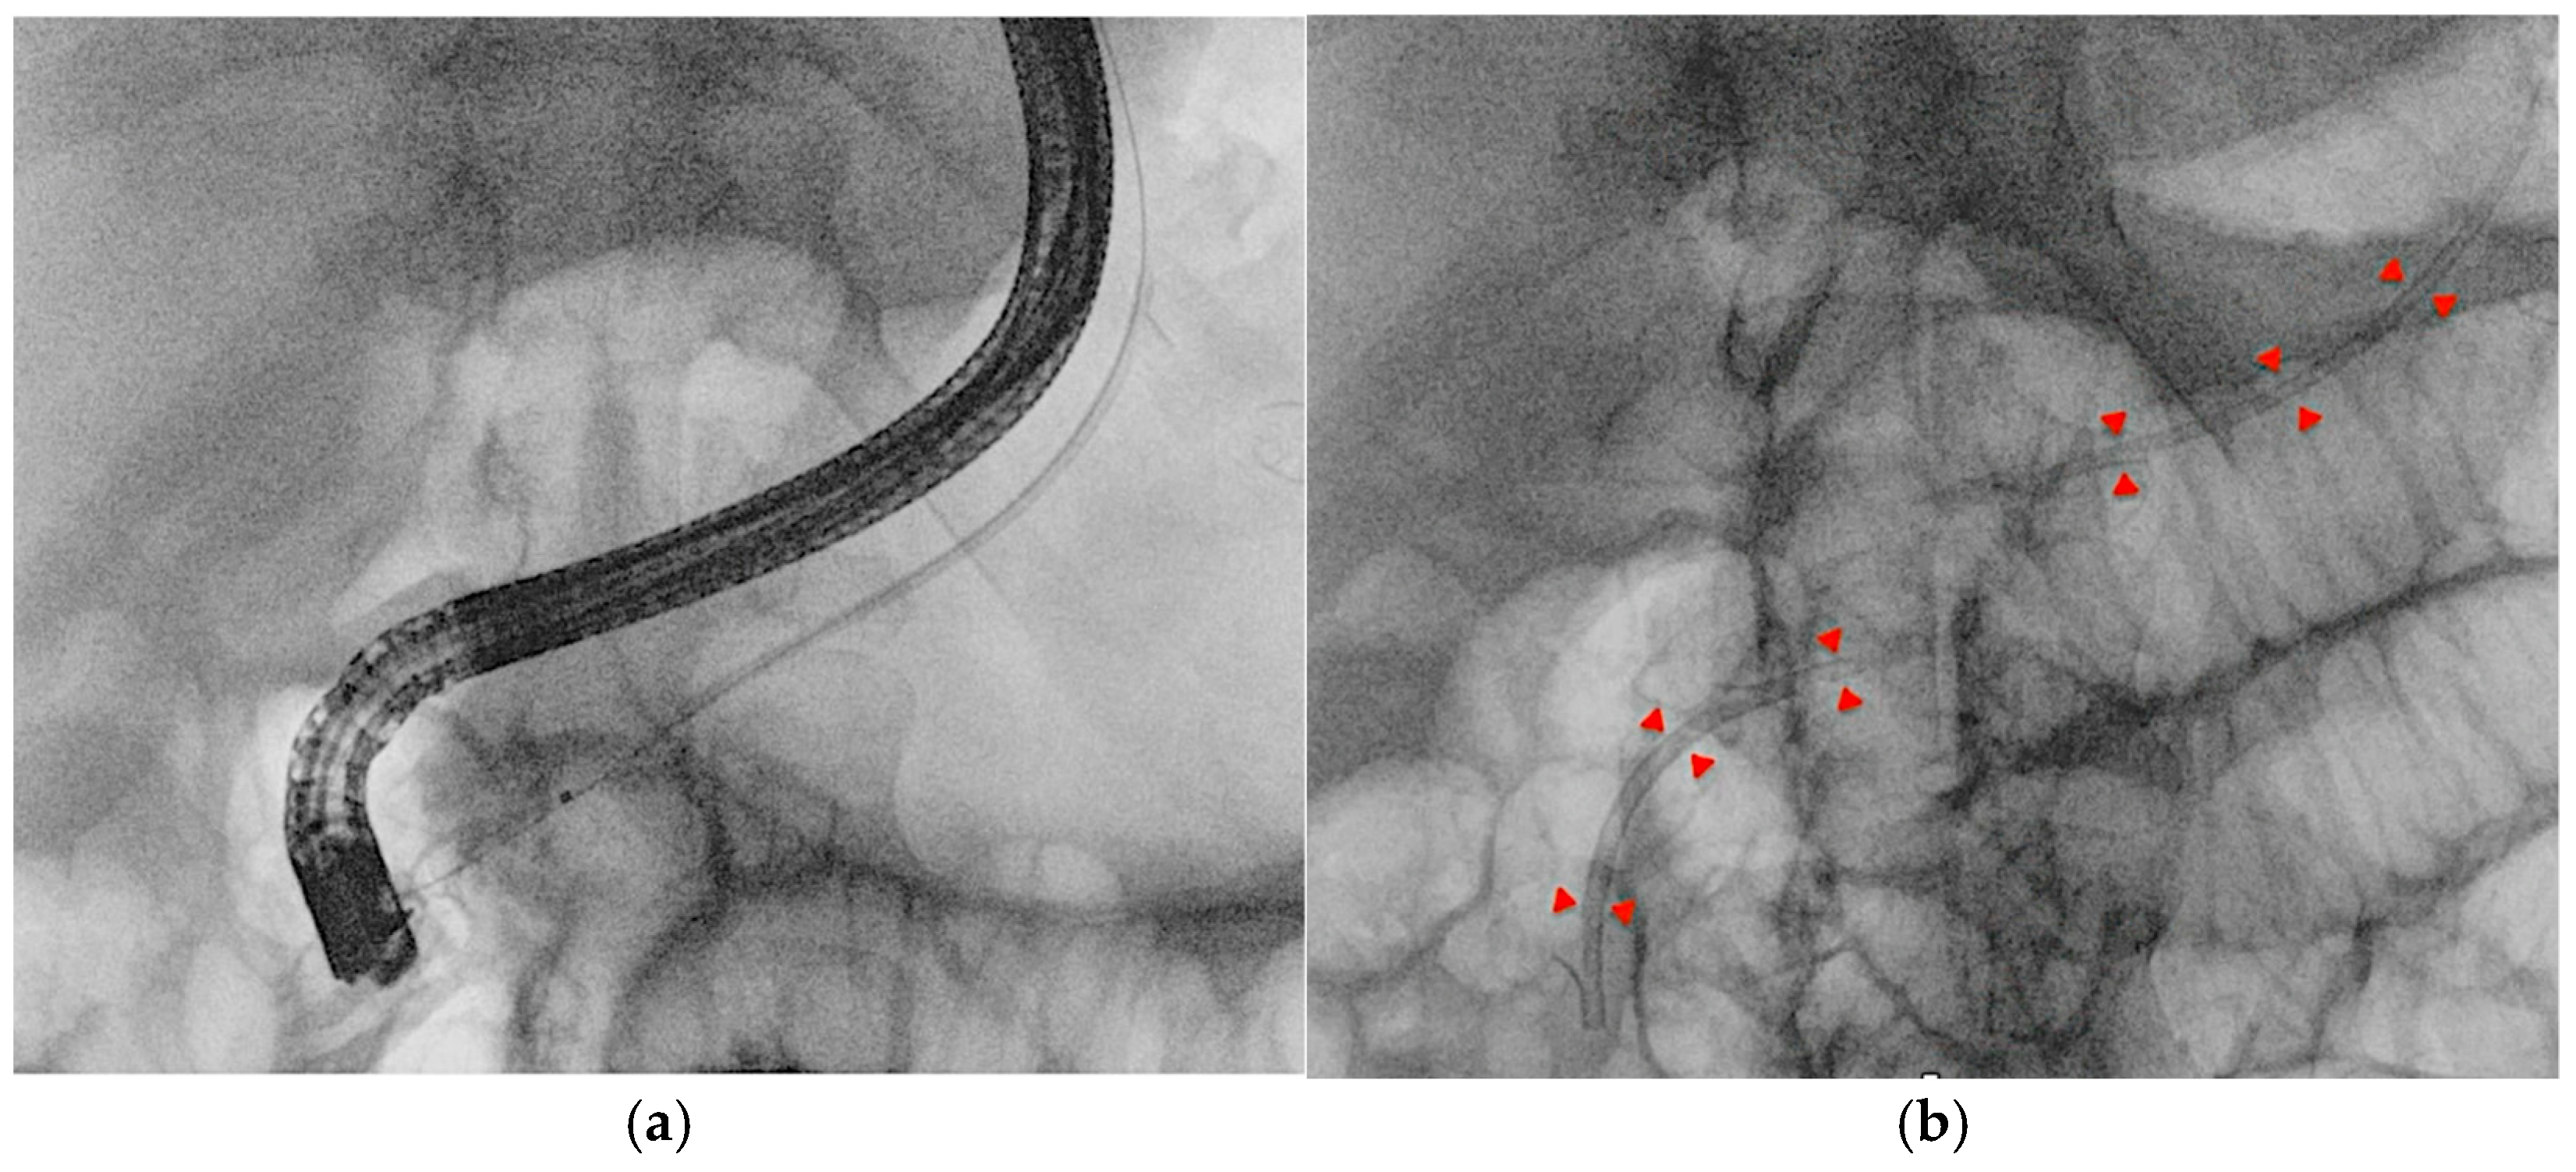

3.1. Biliary Duct Cannulation

Guidewires are essential in the early stages of ERCP. A pivotal 2004 study by Fausto Lella demonstrated the superiority of wire-guided cannulation (WGC) over contrast-assisted methods [21]. The WGC technique has widely become the first-line approach to biliary cannulation [22]. Both techniques require fluoroscopy, as guidewires, like contrast agents, have a radiopaque core visible on radiological images. In WGC cannulation, the guidewire is introduced through the papilla using a sphincterotome or cannulotome, and fluoroscopy enables real-time visualization for selective biliary or pancreatic duct cannulation (Figure 4a). Studies show that this technique increases the success rate, reduces papillary trauma, and minimizes contrast injection into the Wirsung duct, lowering post-ERCP pancreatitis rates [23]. A meta-analysis of RCTs confirmed that WGC cannulation significantly improves biliary cannulation rates (OR: 2.05, CI: 1.27–3.31) and decreases post-ERCP pancreatitis (OR = 0.23, CI: 0.13–0.41) [24]. In the case of trainees, who often take longer to perform ERCP, an RCT indicated that angled guidewires led to higher successful selective biliary cannulation rates compared to straight guidewires. The limitations of the study are the small sample size and the definition of difficult biliary cannulation set at 7 min, which could be equivocal [25]. The typical WGC involves loading a straight guidewire onto a sphincterotome, but for trainees with limited experience, the angle of an angled one can assist in achieving successful cannulation. A recent RCT involving 588 patients compared exclusive WGC with the hybrid technique, in which small amounts of contrast are injected into the distal bile and pancreatic ducts when the infundibulum of the papilla of Vater is cannulated to help orient the papillotome or guidewire axis toward the biliary tree. The results of this study showed faster biliary cannulation, a shorter total ERCP time, reduced need for precut, and less inadvertent intubation of the Wirsung duct, which was identified as a greater risk factor for PEP than inadvertent contrast injection into the pancreatic duct (OR 4.22 vs. 2.63). However, along with these potential beneficial factors, PEP occurred at similar rates in both groups. The limitations of the study include its single-center design, the lack of a standardized threshold for precutting, and the absence of prophylactic measures in both groups [26]. Selective biliary cannulation using conventional techniques fails in up to 18% of native papilla cases [22]. In difficult cases, the “double guidewire technique” (DGW-T) is often employed, where one wire is placed in the Wirsung duct to block the pancreatic orifice, aiding the second wire in cannulating the bile duct (Figure 4b). This technique also helps in identifying papillary anatomy and orienting biliary access [27].

Figure 4. (a) Wire-guided cannulation in ERCP; (b) double-guidewire technique: the first guidewire is positioned in the main pancreatic duct, followed by placement of the second guidewire into the biliary duct.